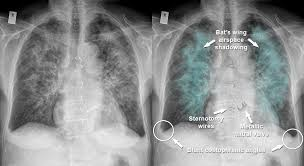

• Pulmonary Oedema

excess fluid in lungs caused by decreased cardiac function/heart failure

bat-wing appearance in imaging